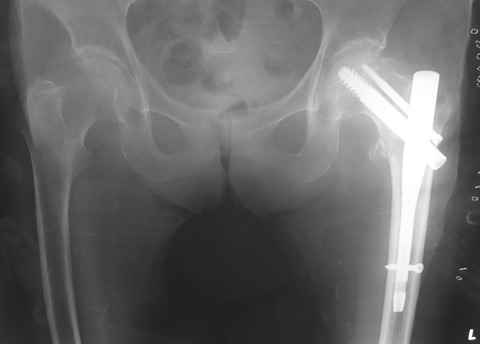

さて、いつものごとく大腿骨近位部骨折用のshort nailを使用しましたが、ちょっとしたピットフォールに陥りました。まずは下の画像をご覧ください。

一見、何の問題も無さそうですが、実は、lag screwの尾側が大腿骨外側皮質から約5mmほど出ています。ちなみにこの両股関節正面像では、そのことを確認することはできません。

lag screwをよく観察するとやや大腿骨頚部前捻角の分だけ回旋しています。つまりlag screwをやや斜めから見ていることになるので、このアングルからは至適な長さなのです。

しかし、実際にはlag screwの正面像で見ると、lag screwの尾側が大腿骨外側皮質から約5mmほど出ていたのです。最後の術中イメージの確認でこのことに気付きましたが時既に遅しです。

術中のイメージでは、この画像の角度でスリーブが大腿骨外側皮質に接しているように見えたので、実際の長さよりも約5mm長いscrewを選択してしまいました。

今回のピットフォールで、術中イメージの画像だけではなく実際にスリーブが大腿骨外側皮質骨に接触している感覚を得るまでスリーブを挿入するべきだということを学びました。

tensor fascia lata等が邪魔をしてスリーブを挿入しづらいことが多々ありますが、やはりlag screwの計測は一番大事なところなので、しっかり皮質骨に当たるまで挿入するべきですね・・・。